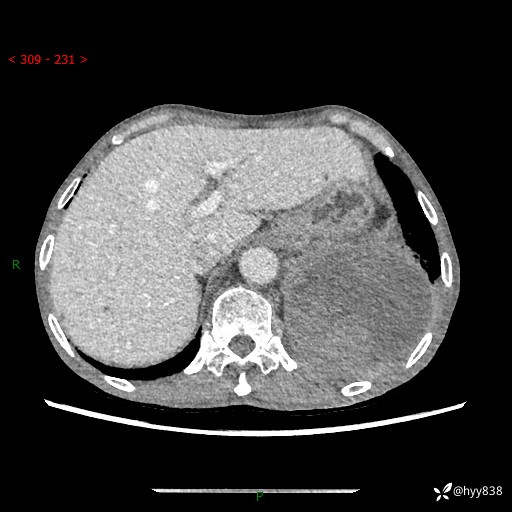

77岁/男,腹痛2月,CT发现左肺占位1天。巨大肿块,肺内或肺外来源…结果公布~

主诉:腹痛2月,CT发现左肺占位1天

现病史:患者于2025年9月间断左下腹胀痛,在当地镇卫生院行彩超检查考虑泌尿系结石,行止痛排石对症治疗未见明显好转;1天前腹痛症状加重,至当地市第三人民医院行CT检查:左肺下叶巨大团块状软组织影,考虑肿瘤性病变,建议增强CT检查;左侧胸腔积液;纵膈内淋巴结肿大;双肺肺气肿;右肺中叶纤维灶。为进一步求治,来我院就诊。

胸部CT平扫+增强